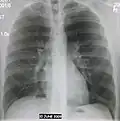

AP CXR showing left lower lobe pneumonia associated with a small left sided pleural effusion -